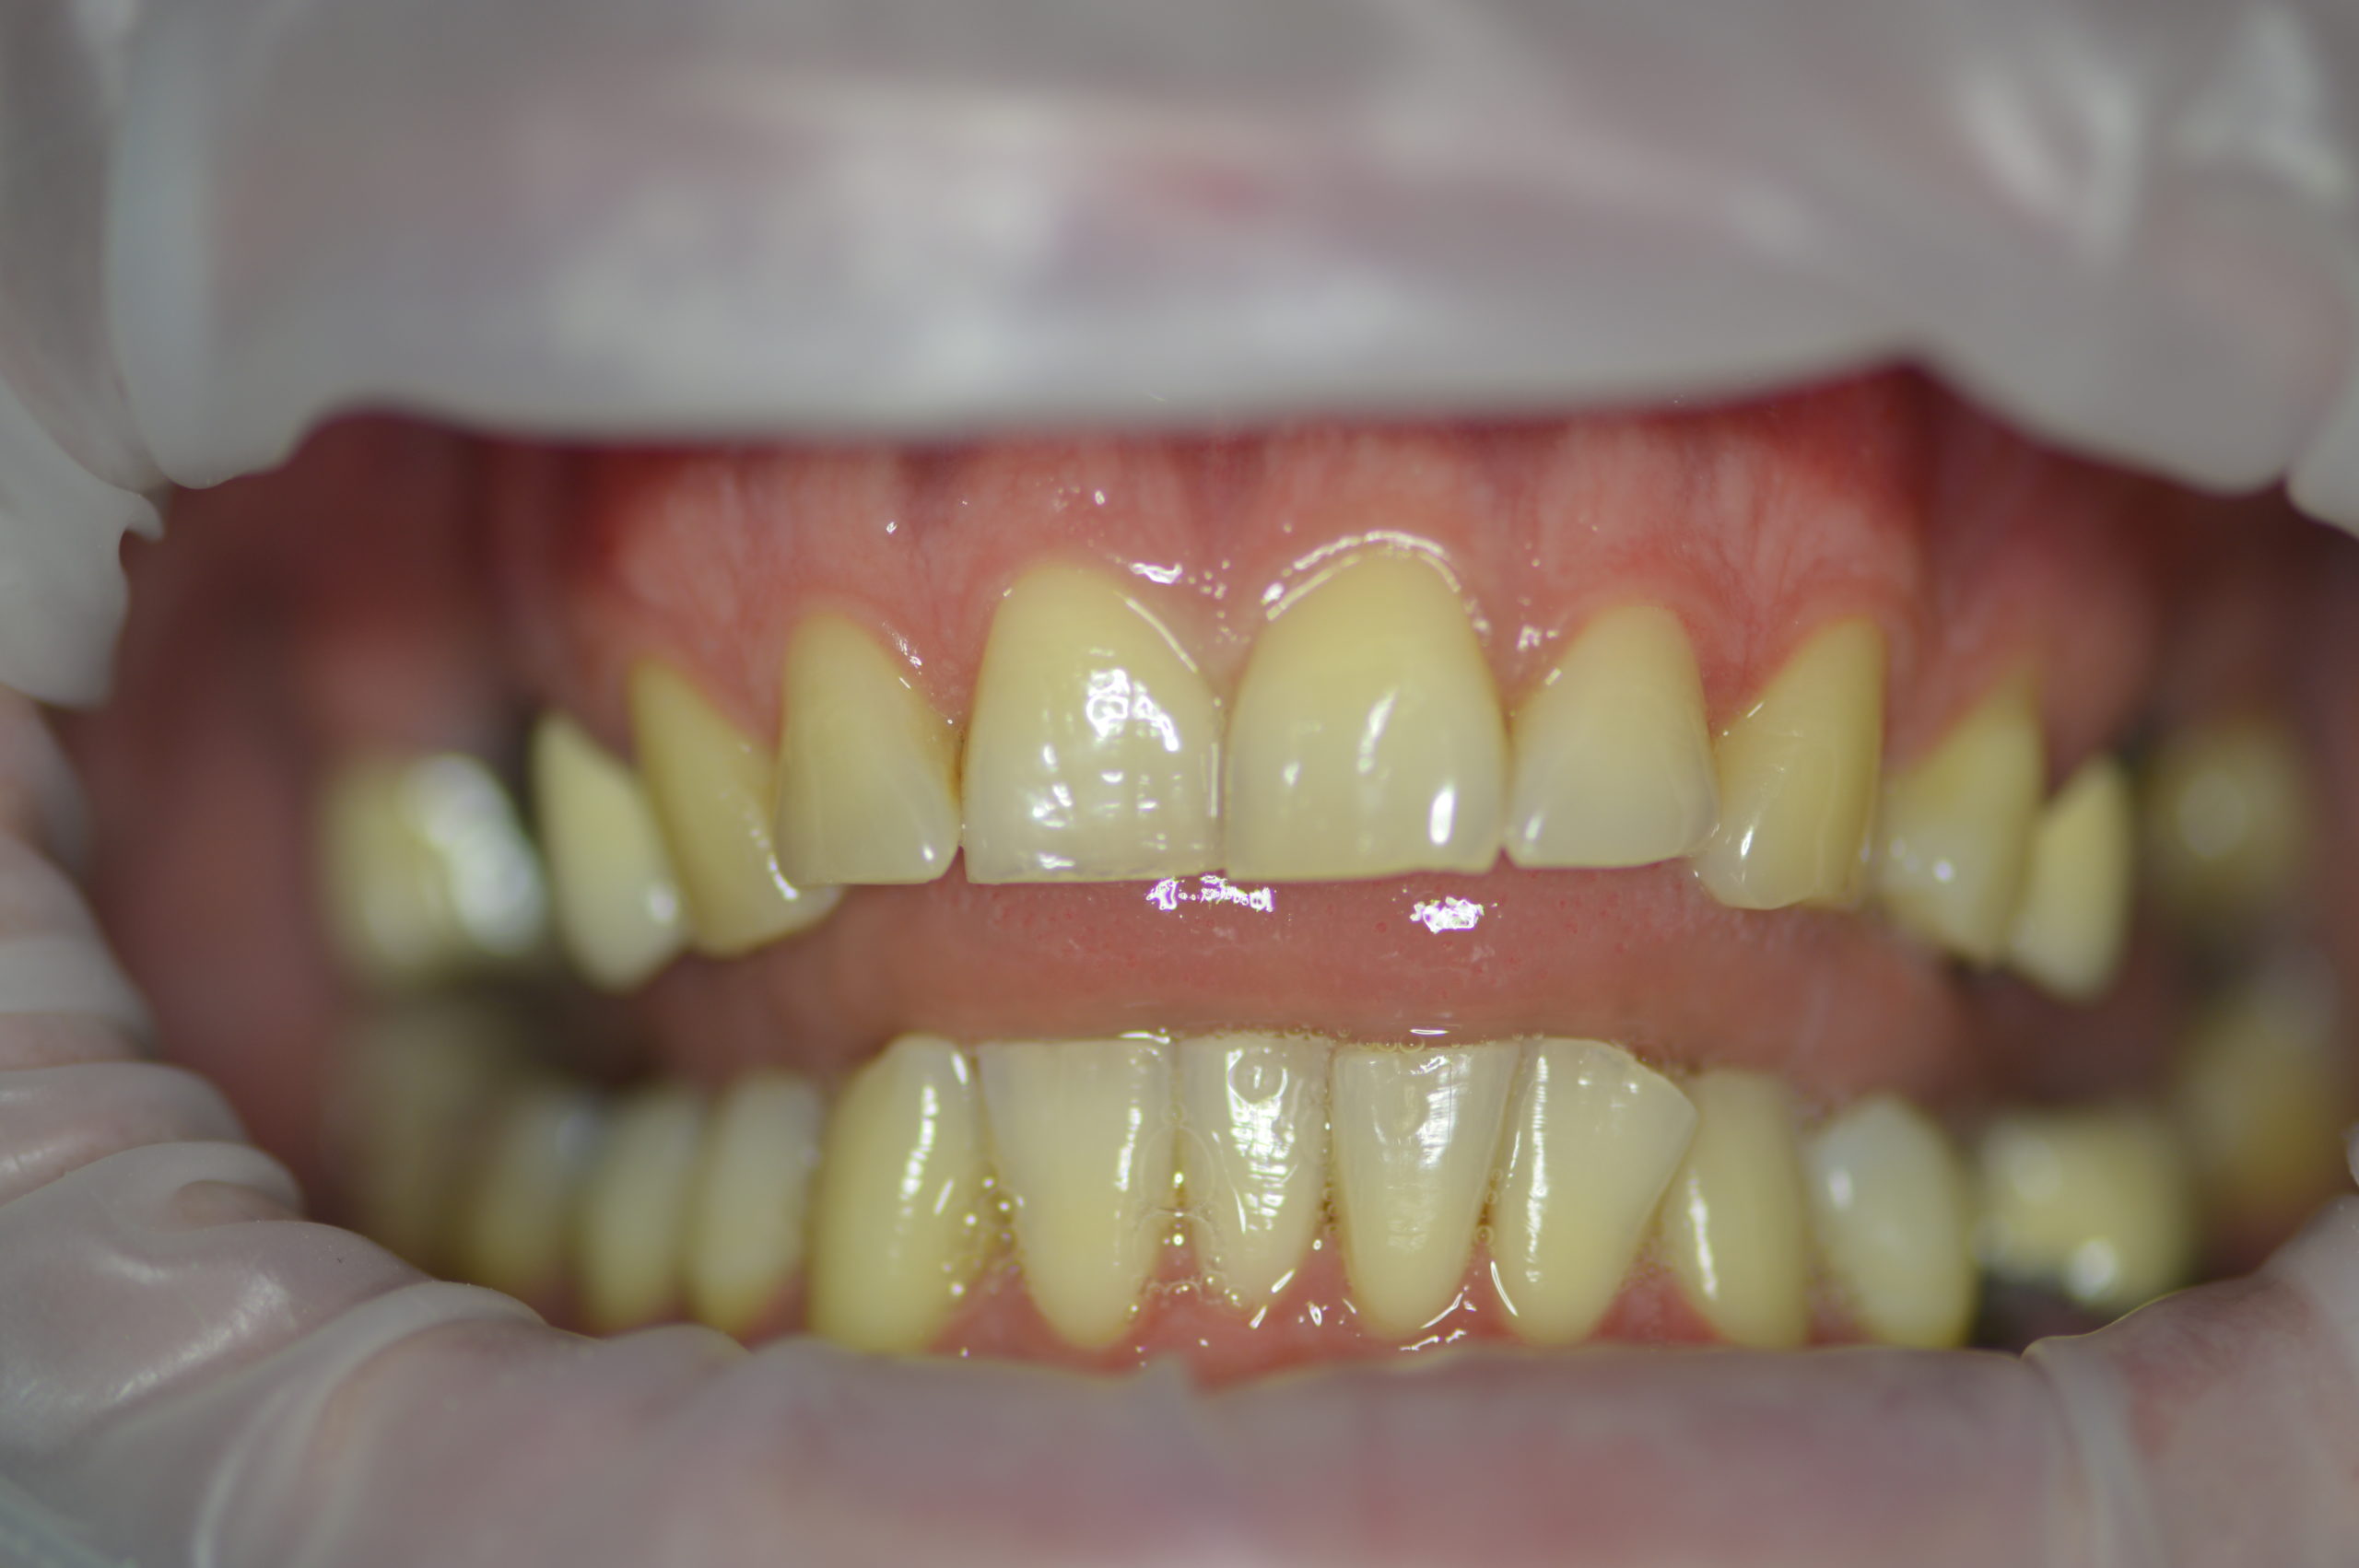

Mr. Peter’s (32 years old) wish was to have nice and bright smile. Dr. Martin made a treatment plan during consultation which contained 6 dental implants (4 for upper jaw and 2 for lower jaw), one tooth extraction, 5 re-root canal treatments and 12 dental crowns. After our patient left the examinaton room, our staff discussed every detail of treatment with him and Mr. Peter made a booking for an implant appointment with Dr.Martin in just 2 weeks after the consultation.